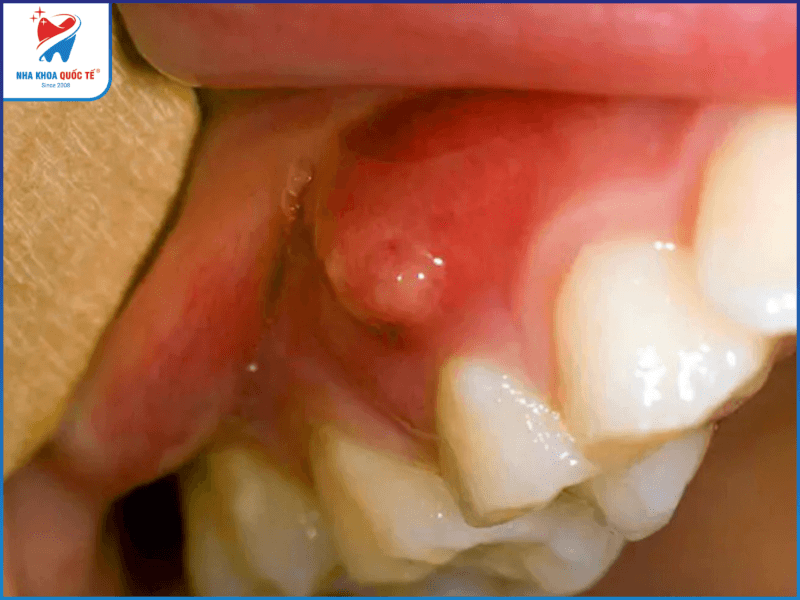

- U chân răng: Bệnh thường không có biểu hiện rõ rệt ở trong thời gian đầu. Tuy nhiên sau khi răng bắt đầu trở nặng sẽ xuất hiện tình trạng chảy mủ, răng bị lung lay và đau ở vùng có khối u.

Đổi màu răng là dấu hiệu phát hiện bệnh u ở răng sớm nhưng thường dễ bị bỏ qua. Chỉ đến răng miệng gặp một số tình trạng nghiêm trọng hơn như chảy mủ, đau ở vùng có u, lung lay răng, sưng mặt… thì mới được người bệnh chú ý và đi tới nha khoa, bệnh viện khám.